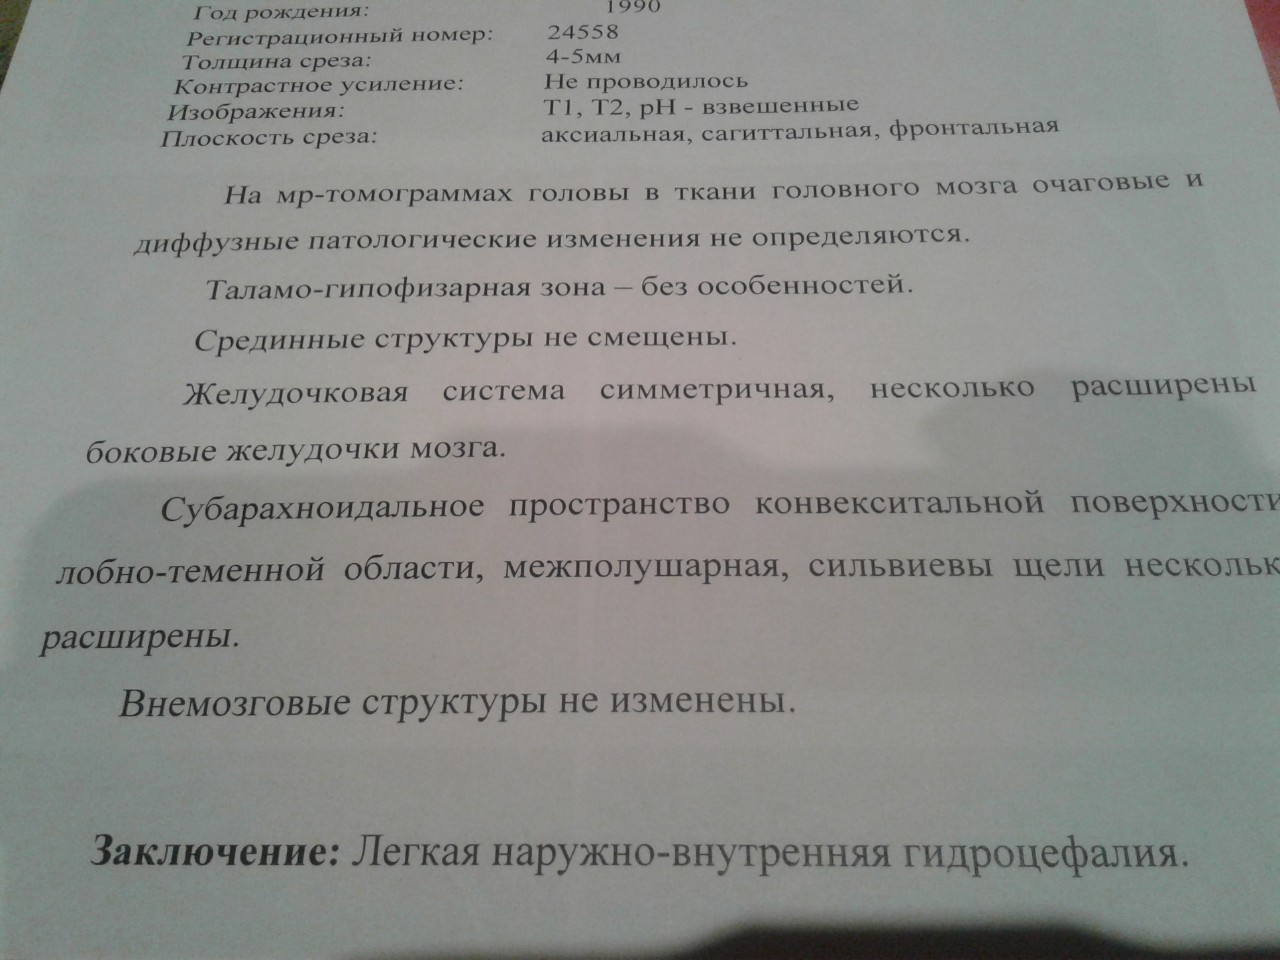

Признаки умеренно выраженной наружная

Признаки умеренно выраженной наружная 113 фото